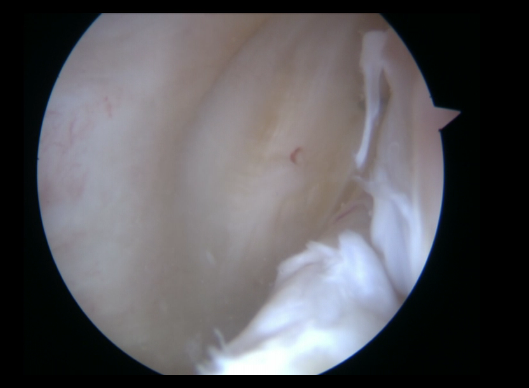

Este tipo de lesiones se pueden clasificar en 5 tipos(5)(Figura 1):

- Tipo 1: lesión de la rampa posterior.

- Tipo 2: lesiones parciales superiores.

- Tipo 3: lesiones parciales inferiores u ocultas.

- Tipo 4: lesiones completas.

- Tipo 5: lesiones dobles.

Figura 1. Visión a través del intercóndilo de lesión inferior oculta, que se detecta con la palpación a través del portal posteromedial.